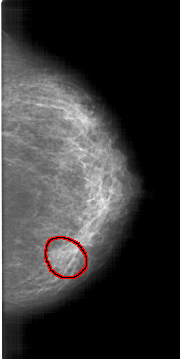

A_1298_1.RIGHT_CC

FILE: A_1298_1.RIGHT_CC.OVERLAY

TOTAL_ABNORMALITIES 1

ABNORMALITY 1

LESION_TYPE MASS SHAPE ROUND MARGINS OBSCURED

ASSESSMENT 4

SUBTLETY 3

PATHOLOGY BENIGN

TOTAL_OUTLINES 1

BOUNDARY